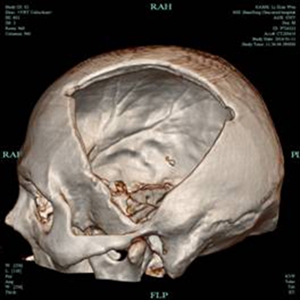

术后2月,患者再次入院,在家属的殷切期望下,我院神经外科积极完善术前准备,排除手术禁忌,于2016年1月14日,在全麻下为患者施行了“颅骨缺损修补术”,置入由计算机预先定制的个体化三维钛网,手术顺利。在十二病区医护的精心照护下,患者恢复顺利,基本恢复了原来的面貌,满意出院。

修补术前 修补术后